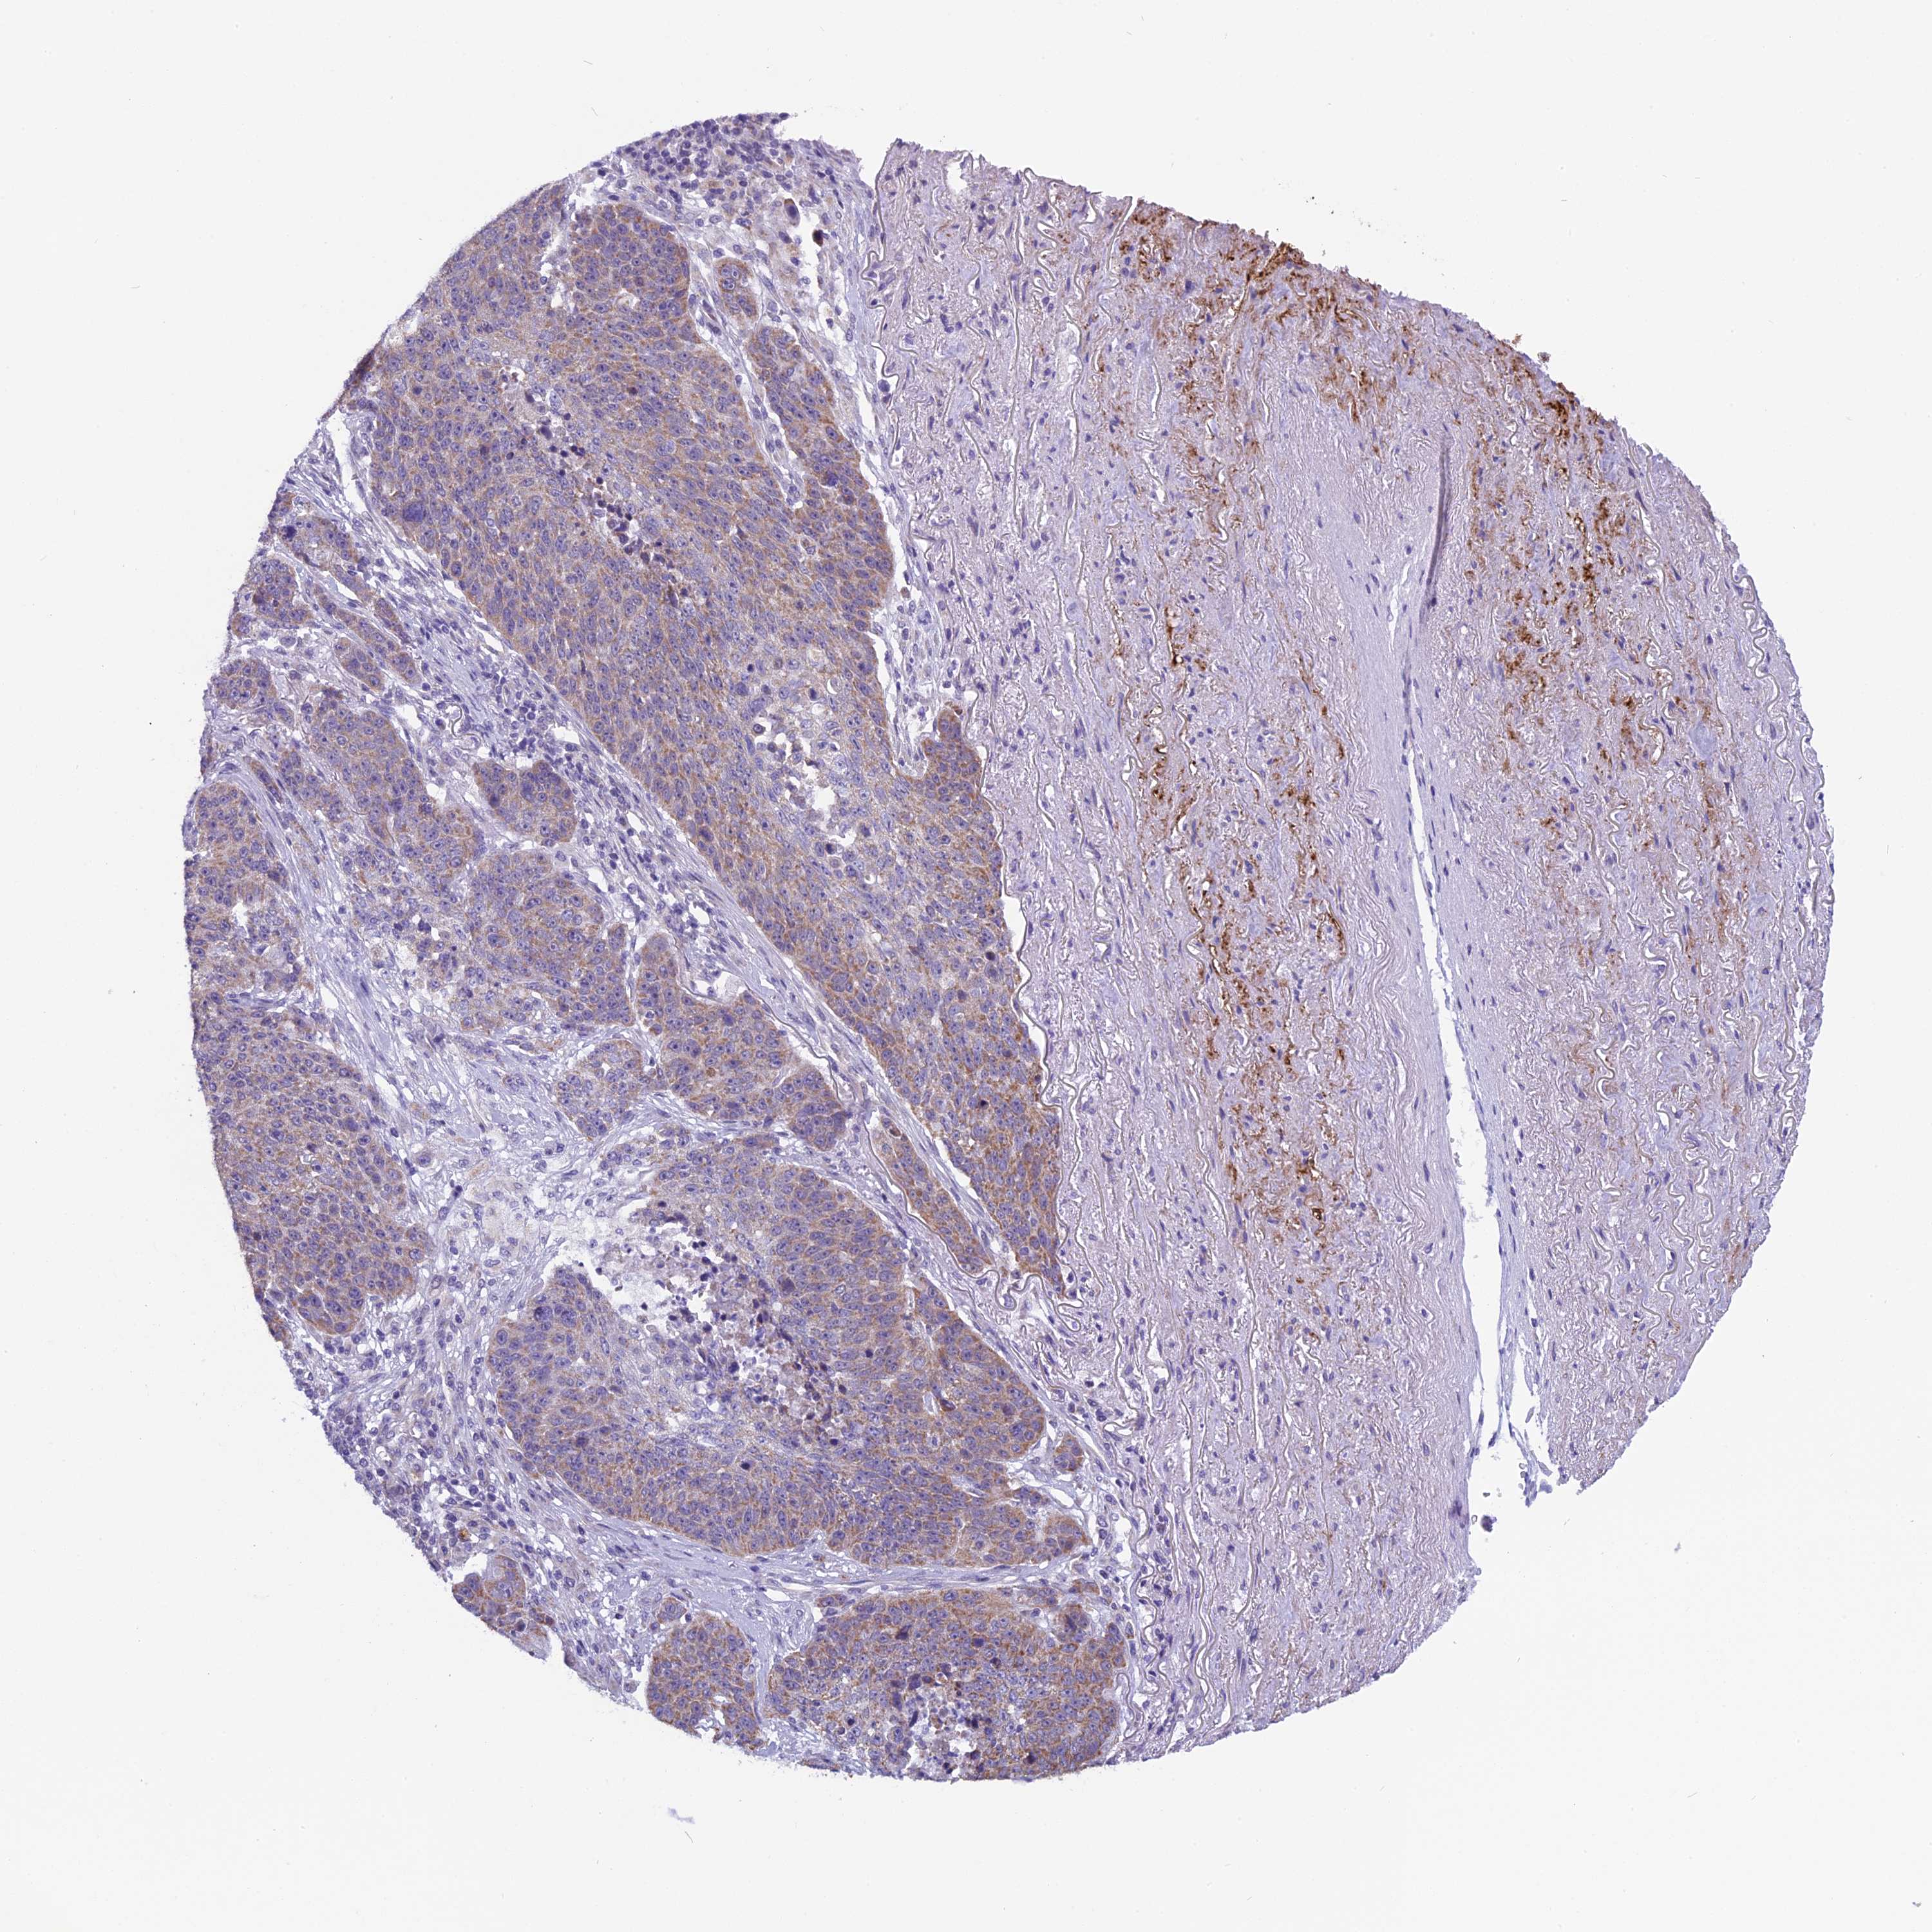

LUNG ADENOCARCINOMA (VALIDATION) - Interactive survival scatter ploti

The Survival Scatter plot shows the clinical status (i.e. dead or alive) for all individuals in the patient cohort, based on the same data that underlies the corresponding Kaplan-Meier plots. Patients that are alive at last time for follow-up are shown in blue and patients who have died during the study are shown in red.

The x-axis shows the expression levels (FPKM) of the investigated gene in the tumor tissue at the time of diagnosis. The y-axis shows the follow-up time after diagnosis (years). Both axes are complimented with kernel density curves demonstrating the data density over the axes. The top density plot shows the expression levels (FPKM) distribution among dead (red) and alive patients (blue). The right density plot shows the data density of the survived years of dead patients with high and low expression levels respectively, stratified using the cutoff indicated by the vertical dashed line through the Survival Scatter plot. This cutoff is automatically defined based on the FPKM cutoff that minimizes the p-score. The cutoff can be changed by dragging the vertical line or by entering a cutoff value in the square labeled "Current cut-off".

Under the Survival Scatter plot the p-score landscape (black curve; left axis) is shown together with dead median separation (red curve; right axis). Dead median separation is the difference in median mRNA expression between patients who have died with high and low expression, respectively. It is calculated as follows: median FPKM expression of dead patients with high expression - median FPKM expression of dead patients with low expression. This is intended to aid the user in visually exploring custom cutoffs and the associated p-scores and dead median separation.

Individual patient data is displayed and can be filtered by clicking on one or more of the category buttons on the top of the page. Categories describing expression level and patient information include: high, low, alive, dead, female, male and tumor stages. The scale of the x-axis can be toggled between linear and log-scale by clicking on the "x log" button. Mouse-over function shows TCGA ID, patient information and mRNA expression (FPKM) for each patient.

& Survival analysisi

Kaplan-Meier plots summarize results from analysis of correlation between mRNA expression level and patient survival. Patients were divided based on level of expression into one of the two groups "low" (under cut off) or "high" (over cut off). X-axis shows time for survival (years) and y-axis shows the probability of survival, where 1.0 corresponds to 100 percent.

ZNF317 is not prognostic in Lung Adenocarcinoma (validation)

Best expression cut offi

Based on the FPKM value of each gene, patients were classified into two groups and association between prognosis (survival) and gene expression (FPKM) was examined. The best expression cut-off refers the FPKM value that yields maximal difference with regard to survival between the two groups at the lowest log-rank P-value. Best expression cut-off was selected based on survival analysis .

When clicking on this number, the vertical dashed line indicating cut-off, the interactive survival plot, and the Kaplan-Meier curve will be adjusted to show results based on the best expression cut-off.

: 12.31

P scorei

Log-rank P value for Kaplan-Meier plot showing results from analysis of correlation between mRNA expression level and patient survival.

N/A

TCGA RNA samplesi

RNA-seq data is reported as average FPKM (number Fragments Per Kilobase of exon per Million reads), generated by the The Cancer Genome Atlas (TCGA) .

Normal distribution across the dataset is visualized with box plots, shown as median and 25th and 75th percentiles. Points are displayed as outliers if they are above or below 1.5 times the interquartile range. FPKM values of the individual samples are presented next to the box plot.

Average pTPM 14.3

Number of samples 105